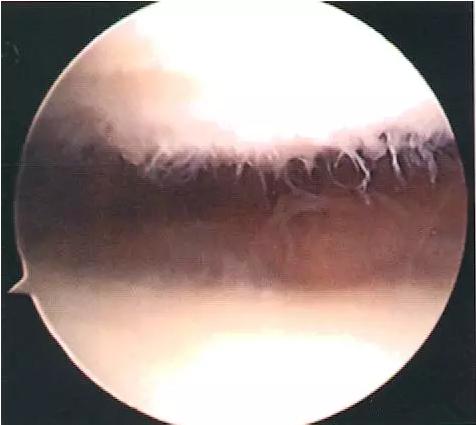

关节镜下见髌骨内缘软骨:“毛刷状”或“纤毛化”改变(如上图)。